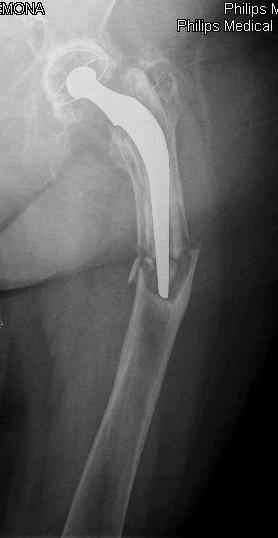

Спасибо за обсуждение. После нескольких дней тракции аппаратом сделали. Попытка закрытой репозиции не удалась из-за смещения по ширине, мешали фрагменты цемента. После их удаления репозиция получилась. Еще убрали немного цемента с ножки по латерльной стороне, чтобы обнажить 40-50 мм ее дистальной части, для плотной посадки гвоздя. Дальнейшее введение гвоздя было несложным. Протез показался нам стабильным в проксимальной части как латерально, так и медиально. Картинки в приложении.

THX for the discussion. After few days of traction by ex-fix the surgery was performed. An attempt of closed nailing was unsuccesful because of fragment translation, which was blocked by cement fragments. After removal of broken cement pieces reduction was reached "automagically". Also some cement from lateral part was removed by

chisel to expose distal 40-50 mm of the stem to allow tight fit of the nail. Further fixation by the nail was pretty easy and straightforward. Images attached. The stem looked stable in its proximal part both laterally and medially. Comments/critics are welcome.

X-rays look very good .... it would be nice to have follow up as well, please?